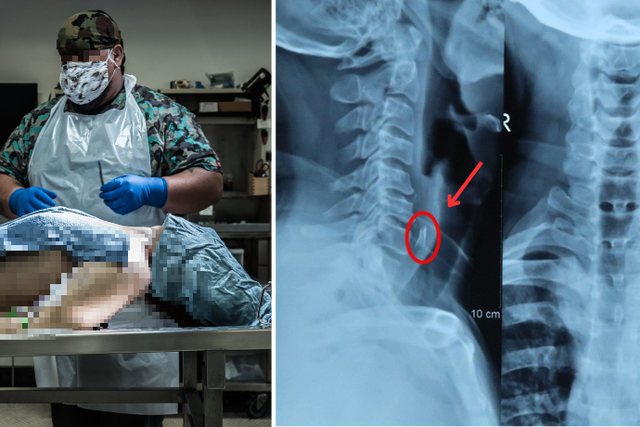

Sự việc càng trở nên kỳ lạ khi bác sĩ Santu Bag tiến hành khám nghiệm tử thi thì phát hiện một thứ đáng sợ.

Kết quả khám nghiệm tử thi đưa ra khiến ai cũng sốc. Ảnh minh họa

Theo báo cáo trên trang India Today, bác sĩ đã phát hiện một con gà con còn sống, dài gần 20cm, nằm dài trong thực quản của nạn nhân. Chính con gà này đã chặn đường thở, dẫn đến cái chết thương tâm của anh Yadav.

Thông tin này khiến gia đình anh Anand Yadav và những người chứng kiến không khỏi bàng hoàng. Thậm chí chính bác sĩ khám nghiệm tử thi cũng cho biết: "Trong suốt 15.000 ca khám nghiệm tử thi của mình, tôi chưa từng gặp trường hợp nào tương tự. Sự việc này khiến tất cả chúng tôi đều sốc".